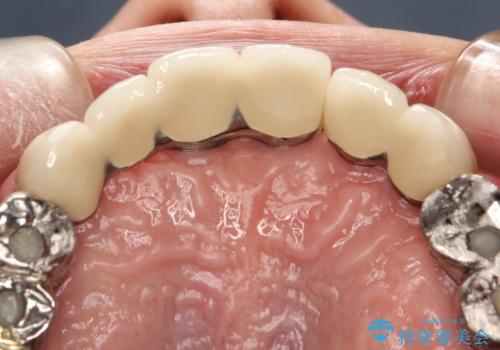

虫歯だらけ、歯周病 崩壊した口腔の再建 フルマウスリコンストラクション

- 歯周外科・インプラント・顕微鏡下根管治療などを含んだ総合的な治療を計画した。

様々な治療手段を高いレベルで同時に併行して行うことが必要でした。

かみ合わせの力が非常に強く、夜間の歯ぎしり・食いしばりもひどかったため、奥歯はメタルオクルーザルの設計でかぶせ物を製作しています。

かぶせ物の種類:PFZ / PFM metal occlusal